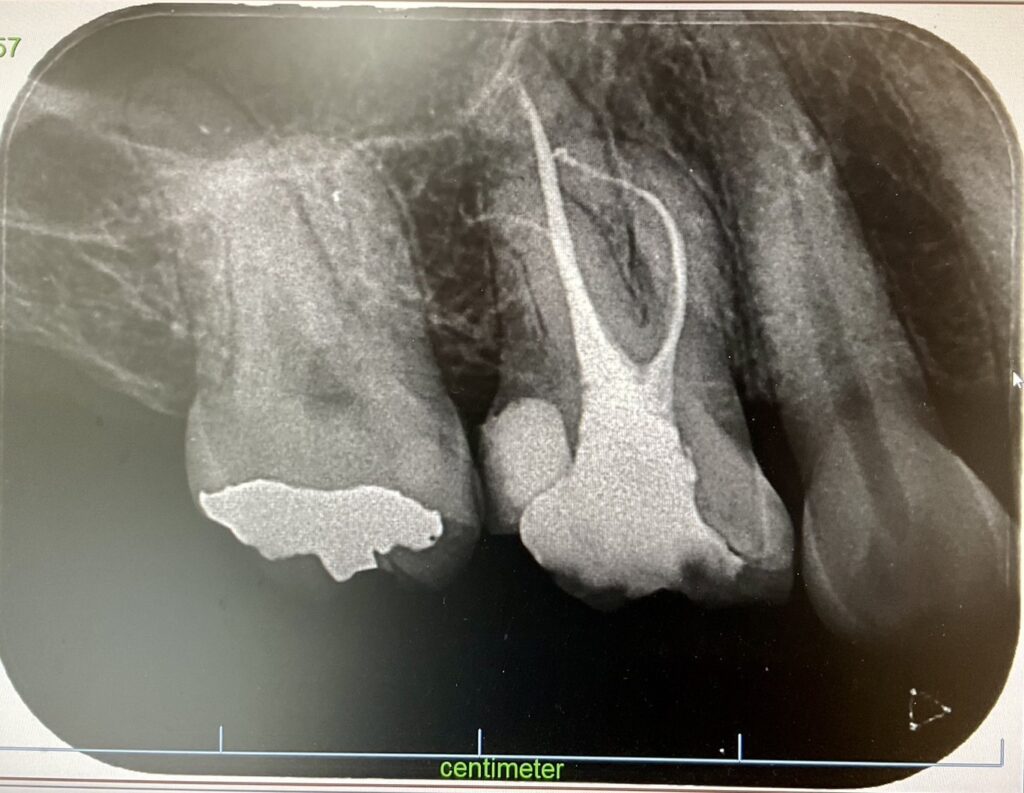

Wave one gold で抜随後、垂直加圧根管充填を行なったデンタルX線像